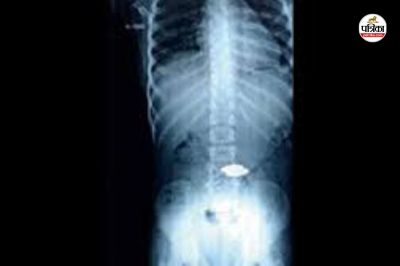

उसके हाथ-पैर ठंडे पड़ने लगे। परिजन फिर शिवम को मेडिकल कॉलेज अस्पताल कोरबा लेकर पहुंचे। यहां उन्होंने डॉक्टर की सलाह पर शिवम की एक्स-रे कराई गई। रिपोर्ट में सीने में सिक्के जैसी चीज फंसने की पुष्टि हुई। डॉक्टरों ने बच्चे की स्थिति को गंभीर बताया। उसकी बिगड़ती हालत को देखकर उसे इलाज के लिए मेडिकल कॉलेज के डॉक्टरों ने दूसरे अस्पताल रेफर कर दिया।

बच्चे की स्थिति पहले से नाजुक थी। इलाज के दौरान प्रारंभिक जांच में बच्चे सीने में सिक्के के आकार जैसा कुछ होने की अंदेशा था। बच्चे की मृत्यु के बाद उसके शव का पोस्टमार्टम कराया गया है। रिपोर्ट में बच्चे के सीने में सिक्का नहीं मिला है। संभावना है कि उसकी मौत एम्बोलिज्म की वजह से हुई है।